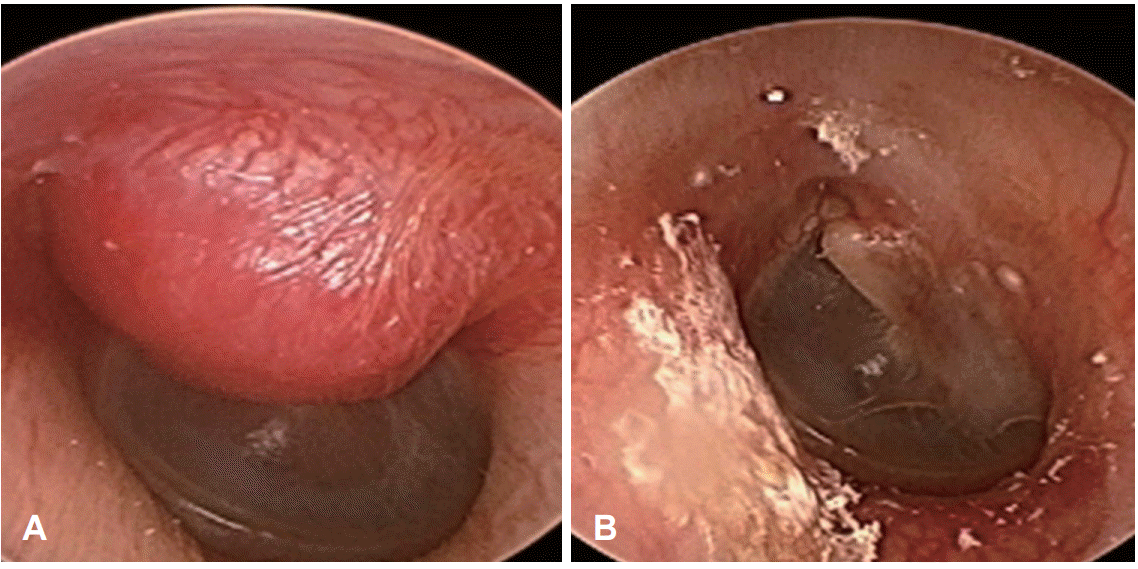

45세 남자 환자가 4개월 전부터 하루 종일 심장박동과 같이 뛰는 듯하게 지속되는 좌측의 박동성 이명을 주소로 내원하였다. 환자는 좌측 박동성 이명 이외의 청력저하, 이통, 이루, 현훈, 안면마비 등의 소견은 보이지 않았다. 특별한 기저질환은 없었으며 가족력 및 과거력상에서도 특이병력은 없었다. 외이도와 고막의 이경검사에서 좌측 외이도 후상방에 표면이 매끄럽고 경계가 명확한 적색의 종물이 관찰되었고 고막은 종물로 인해 반 정도 가려져 있었다(Fig. 1A).

Fig. 1.

The photographs of preoperative (A) and postoperative (B) otoscopic findings. Preoperative otoscopic finding of the left ear shows a pinkish to reddish colored mass in the external auditory canal (EAC) (A). Postoperative otoscopic finding of ear shows a normal tympanic membrane and EAC (B).

환자는 수술 직후부터 박동성 이명이 소멸되었으며, 특이한 합병증 없이 수술 후 2일째에 퇴원하였다. 수술 후 3개월 뒤 시행한 이내시경검사에서 정상적인 외이도와 고막 소견을 보이고 있었으며(Fig. 1B), 순음청력검사상에서도 기도 2 dB, 어음명료도는 100%로 정상 청력을 유지하고 있었다(Fig. 2B). 현재 환자는 수술을 시행 받은 지 1년째로 외이도 및 고막에 재발된 소견 없이 정기적인 외래 관찰 중에 있다.